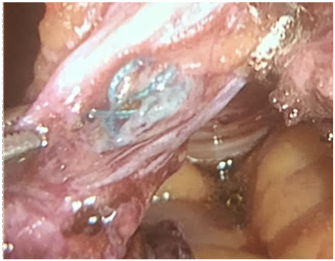

We report a case of a 72 years-old male patient who had history of previous purulent drainage through the belly bottom during the last 18 months. He had undergone to open appendectomy 14 years ago. During these episodes local treatment with topical antibiotics was performed with partial resolution. He came to the clinical office complaining about purulent discharge through the umbilicus again. CT showed a 4 cm fluid collection located in the infraumbilical middle line, communicating with the belly bottom (Figure 1 & 2). The patient accepted to undergo surgery. We performed a laparoscopic approach. Before portal placement and pneumoperitoneum we dissected the infected area inside the umbilicus, sutured with 2-0 Vycril® and left the specimen inside the abdominal cavity. Figure 3 demonstrates our standard ports placement. After this, we placed a 10 mm port, 8 cm above the belly bottom and started the pneumoperitoneum. The camera was placed in this trocar. Another two 5 mm ports were placed lateral to the rectus abdominis, one for a grasper and the other for scissor (Figure 4) Adhesions were perceived during cavity inspection.. We dissected the urachus and. a retained suture material with intense inflammatory reaction was identified (Figure 5). Bladder resection was not needed. The surgical specimen was removed through a 5 mm portal. Fascia was sutured with 0 Vycril®. Estimated blood loss was not quantified. Operative time was 94 min.Patient was discharged 24 h after the procedure and no early or late complications were reported after 60 days of follow-up. Pathology report demonstrated fibrotic connective tissue with chronic inflammation and foreign body granuloma in a 6.0 x 2.0 x 1.8 cm specimen.

Figure 1 & 2 CT sc an demonstrated images suggesting an infected urachusremnant.